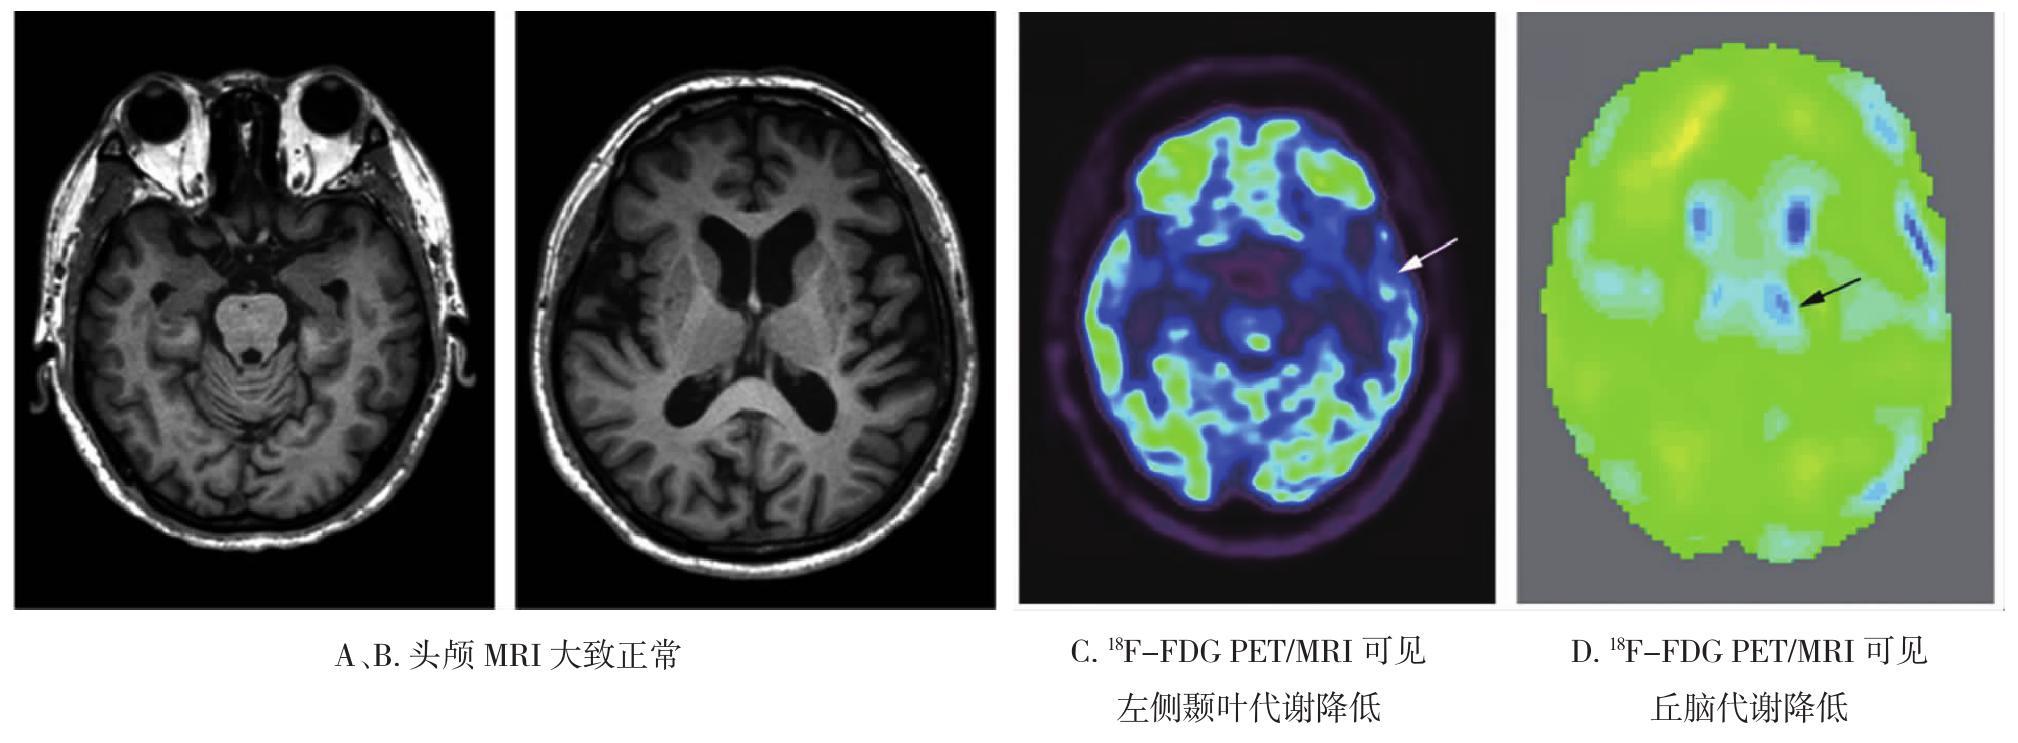

• 皮质基底节变性的影像诊断研究进展

2021, 46(7):818-822. DOI: 10.13406/j.cnki.cyxb.002866

摘要 (70) HTML (289) PDF 1.30 M (184) 评论 (0) 收藏

摘要:皮质基底节变性(corticobasal degeneration,CBD)是一种以不对称的运动症状和大脑皮质功能障碍为主要表现的神经退行性疾病。金标准为病理诊断,临床特征的异质性以及与其他神经退行性疾病在症状和病理方面的重叠性使得诊断难度大。现行诊断标准正确率较低,未将影像学纳入其中。本文主要综述近几十年CBD的影像学进展,包括计算机断层扫描(computed tomography,CT)、磁共振成像(magnetic resonance imaging,MRI)、放射性核素显像等,以及其在疾病鉴别方面的贡献。

• 0+1

• 1+1